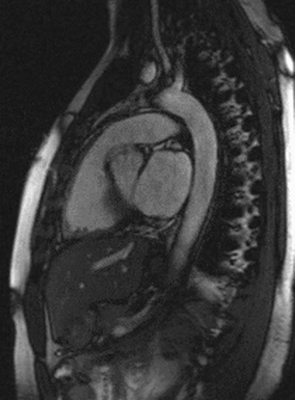

Магнитно-ядерная томография не очень информативна при исследовании костных тканей. Плохо видны на снимках и легкие, в которых слишком много воздуха. В процессе дыхания они двигаются, что не позволяет получить четкие изображения легочных тканей. Чтобы повысить четкость картинки, врач может попросить пациента во время сканирования периодически задерживать дыхание на вдохе. Та же проблема наблюдается при попытке проверить сердечную мышцу — ее ритмичные сокращения мешают обследовать миокард на патологии. Однако временно остановить сердце невозможно, поэтому оно фактически является единственным органом в груди, который проверяют с помощью так называемой синхронизации с пульсом/ЭКГ.

Магнитно-резонансная томография позволяет изучить структуру внутренних органов. Метод дает исчерпывающую информацию о состоянии мягких тканей и менее показателен в отношении костей. МР-диагностику назначают для выявления заболеваний органов грудной клетки. Сканирование в большинстве случаев не является методом выбора для обследования легких, однако позволяет хорошо визуализировать трахею, бронхи, плевру, сердце, тимус, крупные кровеносные и лимфатические сосуды. От того, что показывает МРТ грудной клетки, часто зависит окончательный диагноз. Метод применяют как альтернативу и дополнение к КТ, рентгенографии или УЗДГ (ультразвуковое исследование) сердца.

Делают ли МРТ органов грудной клетки?

Низкая информативность МР-сканирования относительно легких обоснована содержанием в их структуре большого количества воздуха. Из-за малой концентрации водорода и постоянного движения снимки получаются нечеткими. Однако магнитно-резонансная томография позволяет выявить опухоли в дыхательной системе, очаги воспаления, фиброзного перерождения или некроза. С ее помощью исследуют органы средостения.